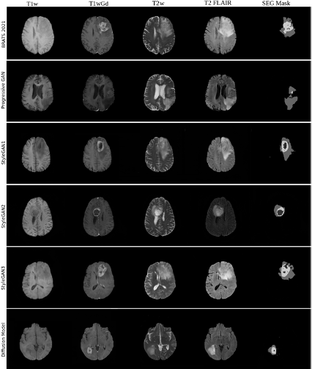

Synthetic brain tumor images

Synthetic brain tumor images from several different GANs and a diffusion model, as well as the trained models, have been shared on the AIDA data hub

This dataset is a collection of synthetic images generated by 5 generative models (Progressive GAN, StyleGAN1, StyleGAN2, StyleGAN3, diffusion model) trained on the BraTS 2020 and 2021 datasets (which share MR volumes from brain tumor patients and the corresponding tumor annotations). The trained generative models are also shared in this dataset.